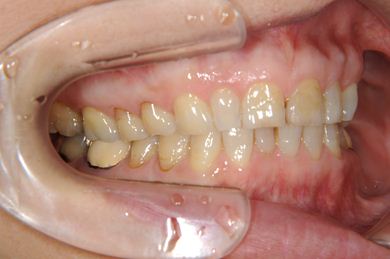

部分矯正治療+セラミック治療

| 性別/年齢 | 女性 / 54歳 | ||||||||||||||||||||||||||||||||

| 主訴 | 下の前歯のゆがみが気になり、相談。 | ||||||||||||||||||||||||||||||||

| 治療方針 | 上顎前歯の叢生を部分矯正にて審美的回復を行い、上顎前歯はラミネートベニアにて審美的回復を行う。 | ||||||||||||||||||||||||||||||||

| 治療内容 | 唇側部分矯正(ホワイト)、オールセラミックラミネートベニア8本 | ||||||||||||||||||||||||||||||||